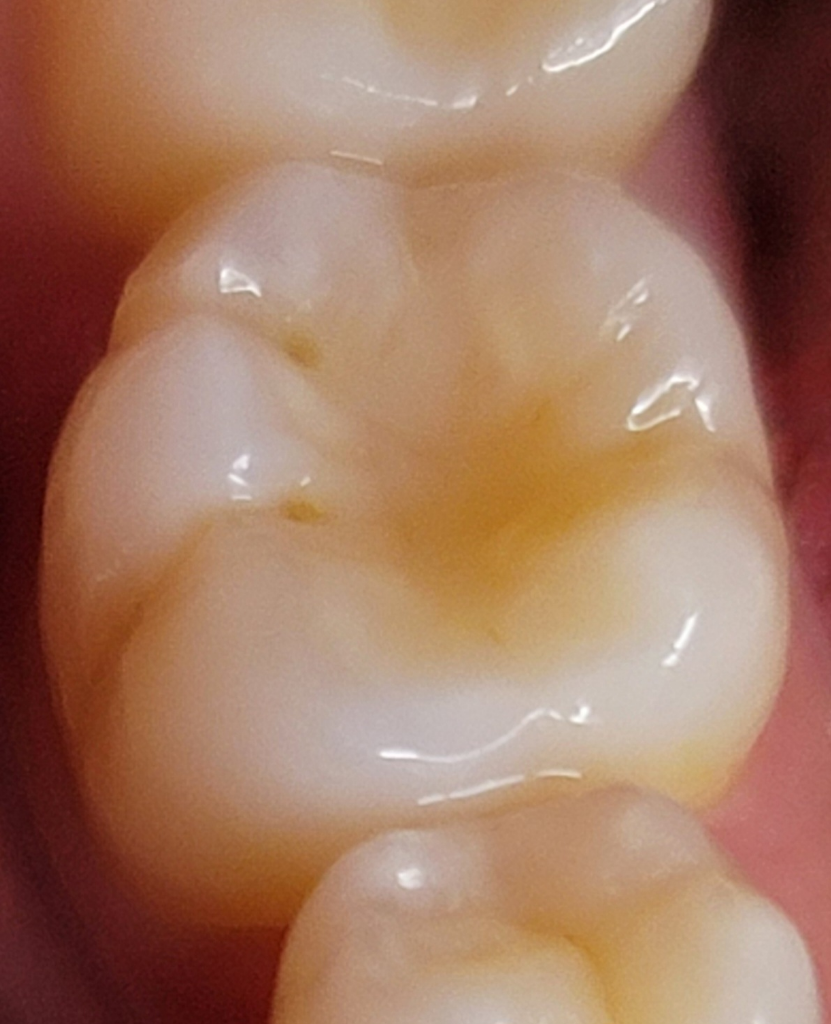

레진 후 치아에 이게 무엇일까요?

약 두달 전 레진 치료한 이빨에 최근 한달 전?부터 두 군데가 사진과 같이 검게 보입니다.. 처음엔 그저 음식물이 끼는 거라고만 생각했는데 저렇게 보여서 ㅜㅜ

치료한지도 얼마 안 됐는데 설마 충치일까요? ㅜㅜ

충치가 아니며 해당 부위는 단순히 상아질이 노출되어 보이거나 빛의 각도에 따라서 약간 어둡게 보이는 것입니다. 충치라면 지금 보다 훨씬 어두워야 합니다. 현재 사진으로 판단했을 때는 충치는 아닙니다.

레진한곳이 시간이 지나면서 구멍이 생긴거 같습니다. 음식물이 끼거나 불편하시면 레진치료를 다시 하셔야될것같습니다.

부분적으로 치아가 마모되어 있는 것으로 보입니다. 별 문제가 아니므로 신경쓰지 않으셔도 됩니다.

레진치료를 한 틈사이로 충치가 발생하였을 가능성이 있으며, 꼼꼼하게 해당부위를 양치하고 관리하길 권합니다. 만약 더 커지거나 진행시 치과 진료를 받길 권합니다.